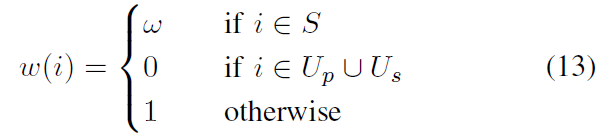

另外,作者认为 Y ^ \hat Y Y^ 可能包括了误分类的像素点,为解决这个问题作者提出将 高不确定性(低 confidence) 的像素点忽略掉,然后再更新网络参数。

不确定性分成两种:

- network-based uncertainty:基于网络的不确定性,其依据网络 softmax 层的输出来确定

- scribble-based uncertainty:基于 scribble 的不确定性

(1)network-based uncertainty

基于 softmax 的输出,如果 p i p_i pi(像素 i i i 属于前景的概率)接近 0.5,就说明该像素点具有较高的不确定性(因为在概率接近 0.5 时无法判断到底属于前景还是背景,相当于瞎猜了)

定义一个像素集合 U p = { i ∣ t 0 < p i < t 1 } U_p = \{ i | t_0<p_i<t_1 \} Up={i∣t0<pi<t1}, t 0 t_0 t0 和 t 1 t_1 t1 是阈值,这个范围内包含了所有不确定性高的像素点 p i p_i pi,而在 p i < t 0 p_i < t_0 pi<t0 时能够确定它是背景,在 p i > t 1 p_i > t_1 pi>t1 时能够确定它是前景。

(2)scribble-based uncertainty

基于到 scribbles 的 geodesic distance(即最小距离)

- G ( i , S f ) G(i,S^f) G(i,Sf):从像素 i i i 到前景像素集 S f S^f Sf 的 geodesic distance

- G ( i , S b ) G(i,S^b) G(i,Sb):从像素 i i i 到背景像素集 S b S^b Sb 的 geodesic distance

设 ϵ \epsilon ϵ 为关于 geodesic distance 的阈值,定义 U s U_s Us 为具有较高 scribble-based 不确定性的像素点的集合, U s = U s f ⋃ U s b U_s = U_s^f \bigcup U_s^b Us=Usf⋃Usb,即分为了前景和背景不确定的点,其分别定义为:

- U s f = { i ∣ i ∉ S , G ( i , S f ) < ϵ , y ^ i = 0 } U_s^f = \{i|i\notin S, G(i, S^f) < \epsilon, \hat y_i = 0\} Usf={i∣i∈/S,G(i,Sf)<ϵ,y^i=0},

- U s b = { i ∣ i ∉ S , G ( i , S b ) < ϵ , y ^ i = 1 } U_s^b = \{i|i\notin S, G(i, S^b) < \epsilon, \hat y_i = 1\} Usb={i∣i∈/S,G(i,Sb)<ϵ,y^i=1}

加权参数可以表示为:

在 fine-tuning 时的权重图(weight map):

- 当像素点具有较高的不确定性时(黑色区域),权重设置为 0;

- 对用户提供的 scribbles(白色线条),权重设置为 ω \omega ω;

- 对分类正确的像素点(灰色部分),权重设置为 1。